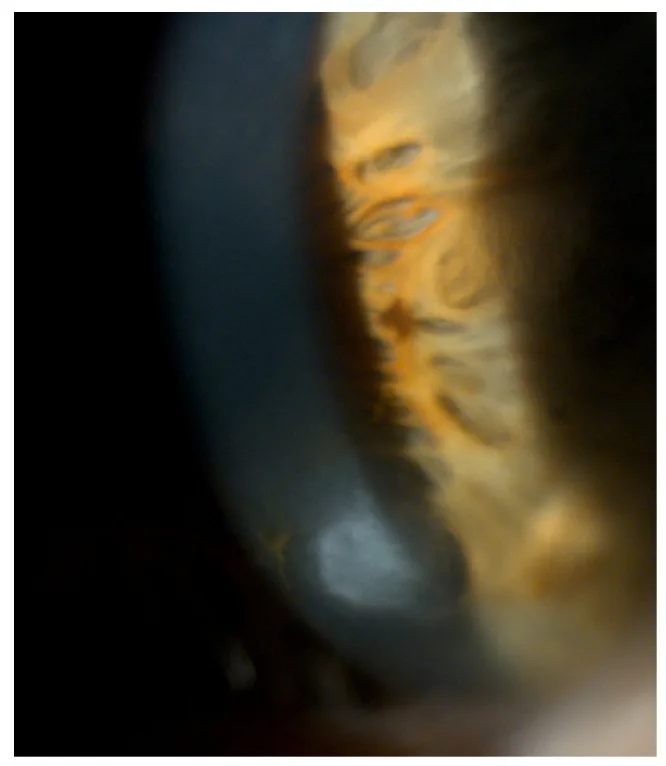

Roszkowska AM, Azzaro C, Calderone A, et al. Salzmann Nodular Degeneration in Ocular and Systemic Diseases. Journal of Clinical Medicine. 2024 Aug 20; 13(4900):$2. Figure 1. PM

CI D: PMC11355337. License: CC BY.

角膜 周辺から前方へ隆起する青白い結節を細隙灯で示している。Salzmann結節の立体感と表層性病変であることが直感的に分かる。